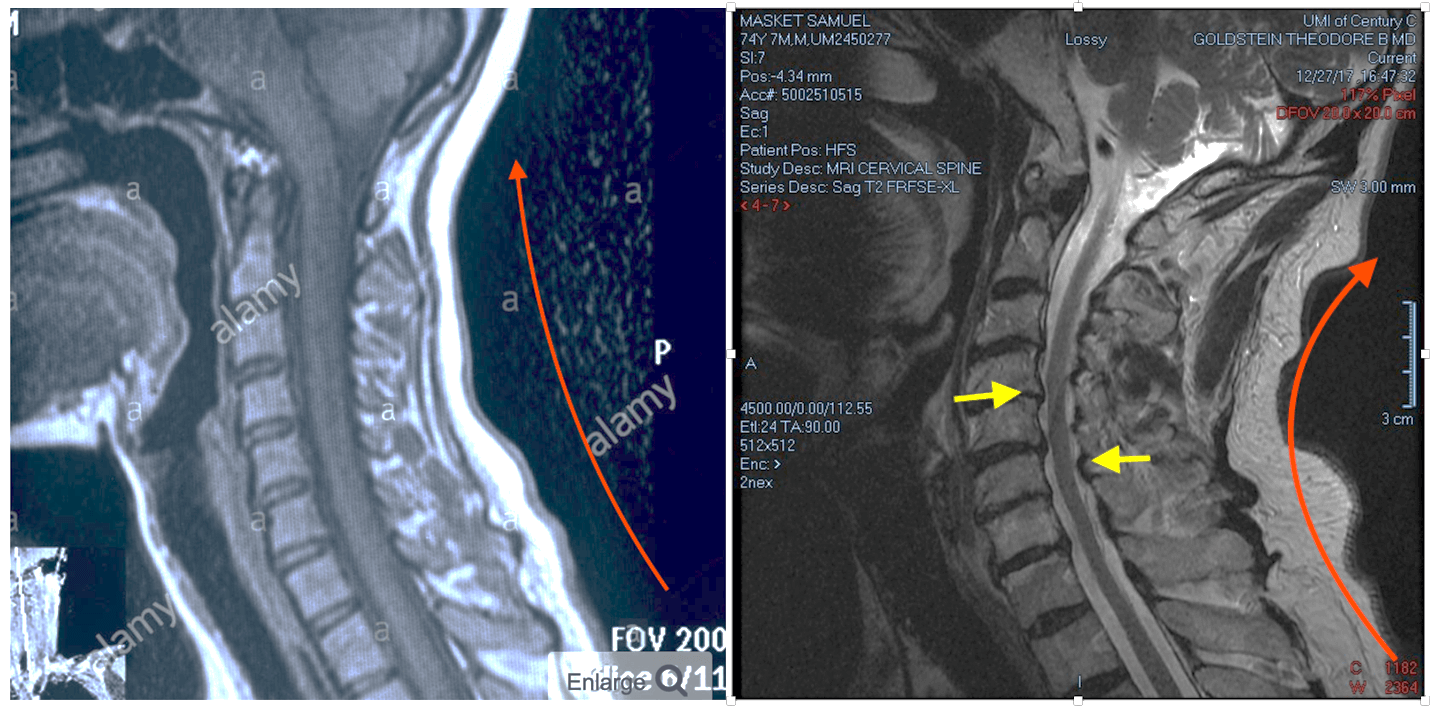

A good example of this is my own neck! You can see the structural changes that have occurred after a long ophthalmology career in my now 74-year-old neck compared with a healthy young adult neck MRI on the left to that of mine (see Figure 2) – particularly the increased lordotic curve (red line) and the stenotic cervical canal (yellow arrows). I have no doubt that the changes in my neck are related to an absence of good ergonomic design and posture planning during my career. Moreover, indirect ophthalmoscopy with a patient whose neck is in an erect position forces the examiner into contortions that will undoubtedly induce fatigue and, later on, structural damage to the back (see Figure 3). During my training program, indirect ophthalmoscope exams were carried out with the patient supine on an examination table, inducing far less stress; however, in daily clinical practice this is impractical.